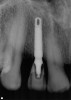

A 54-year-old, non-smoking woman presented with a root fracture at the maxillary right lateral incisor (Figure 1). The patient presented with a 10-mm pocket at the mid-facial probing depth, and a Grade 2 mobility. The preoperative peri-apical digital radiograph can be seen in Figure 2. A natural diastema existed on the distal aspect of the right maxillary incisor, and the patient did not wish to have this corrected. To hold the natural tissue emergence profiles throughout the treatment phase, the immediate implant placement and provisionalization procedure was chosen to treat the affected site. Before the procedure, an occlusal index and registration was taken so that when the retrofitting of the natural tooth shell was accomplished, the exact location of the natural tooth shell could be seated on the implant abutment at the time of implant placement (Figure 3). After administration of an appropriate local anesthetic, tooth No. 7 was removed by an atraumatic technique to preserve the natural soft tissue emergence profiles present pre-surgically (Figure 4). After tooth removal, debridement of the extraction socket was accomplished by curettage of the socket, followed by rotary instrumentation with a course #8 round diamond to ensure removal of all remnants of the periodontal ligament, granulation tissue, and localized debris. To aid in the debridement, the patient was started on a preoperative administration of Augmentin 875 mg, taken the day before treatment, and once again 1 hour before the surgical visit. The patient then continued this antibiotic course for a total of 10 days.

Figure 2  Pretreatment peri-apical radiograph.

Figure 2